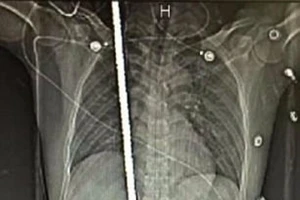

Trắng đêm cứu thanh niên bị thanh sắt 2m đâm xuyên người